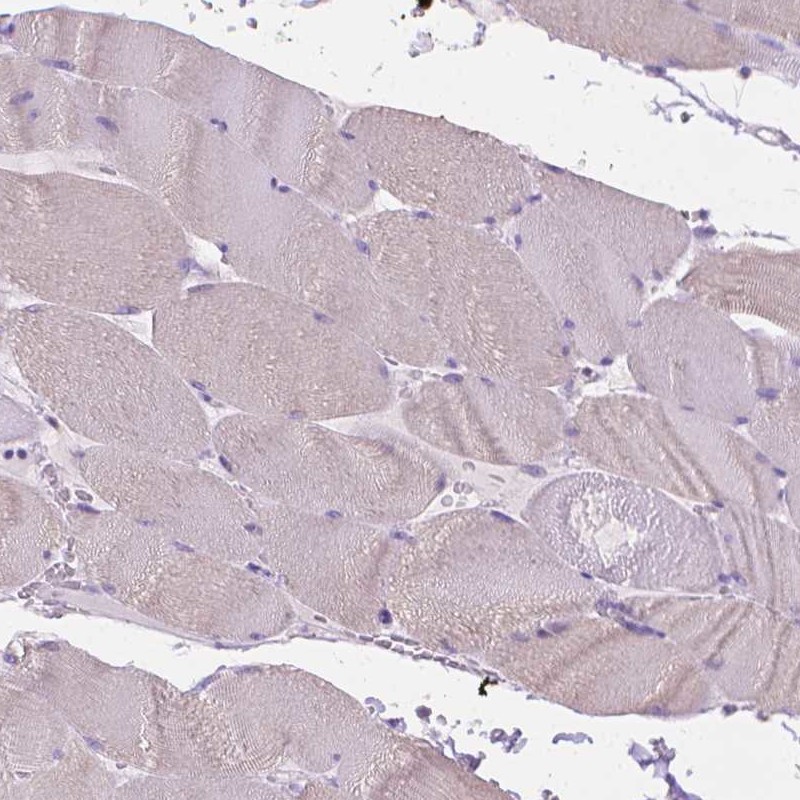

Immunohistochemistry analysis in human breast and skeletal muscle tissues using Anti-FASN antibody. Corresponding FASN RNA-seq data are presented for the same tissues.